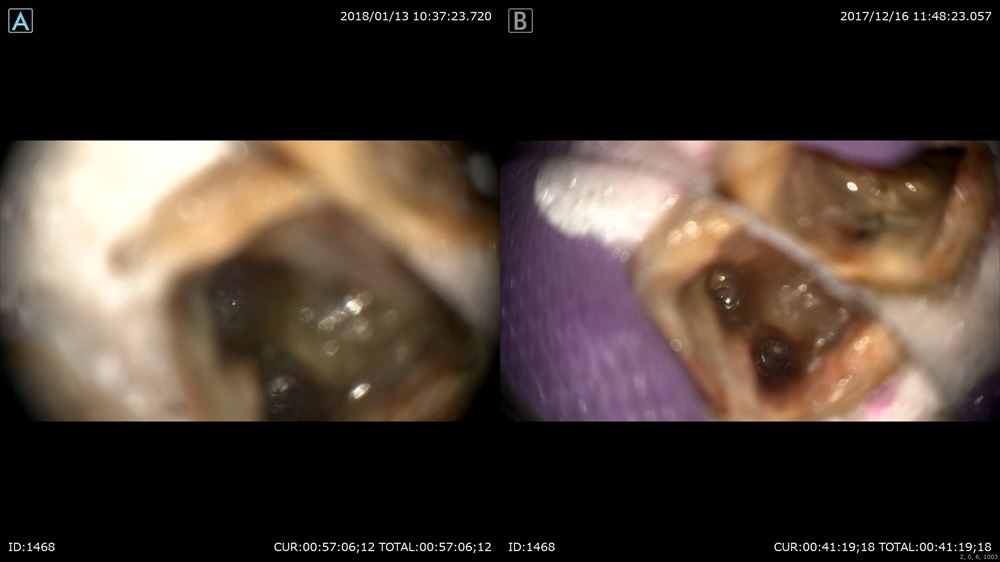

色々な人がきます。この方は他院で治療器具を残されたケース(根管治療に使う器具が根管の中で折れている)症状がなければまだ良いのですが。。症状があります。異物ですので確実に除去したい所です。今日は1時間半の格闘。超音波や色々な最新器具で隙間を器具と歯の間に作ります。0.1mmの世界。

光っているのが金属のリーマーです。

右が術前。左が術後

CTでも確認ML根 術前 ある。

術後 ない!!